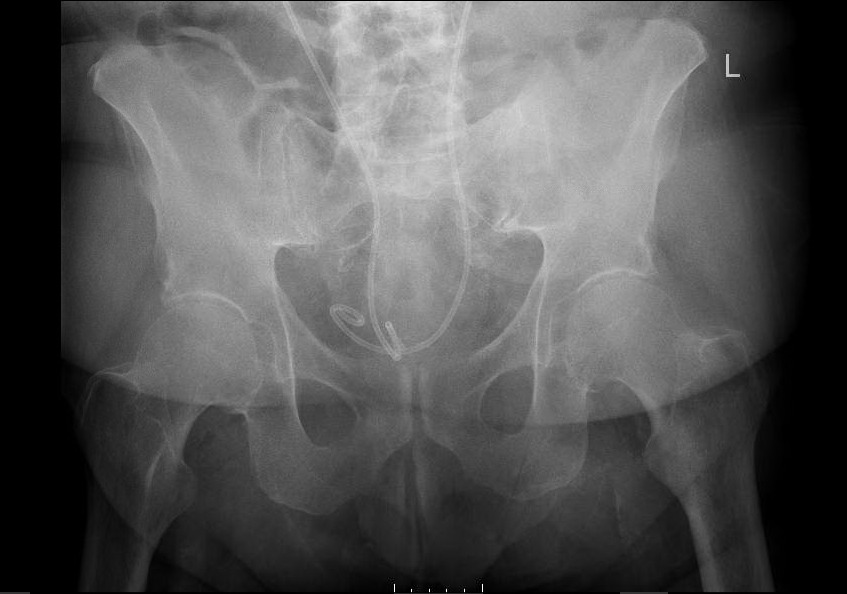

Laboratory studies demonstrated a normocytic anemia, chronic thrombocytopenia, hyponatremia, and chronic kidney disease. His sedimentation rate and c-reactive protein levels were elevated. When the patient was sent over for x-ray imaging, left hip, right hip, and pelvis x-rays demonstrated no abnormalities. Lumbosacral x-ray demonstrated mild scoliosis with diffuse moderate degenerative change. (Image 1) The patient was offered pain medication but refused any other treatment. He was admitted to the hospital due to his intractable bilateral hip pain and inability to ambulate. Orthopedics, Nephrology, and Physical Therapy/Occupational Therapy consults were placed.